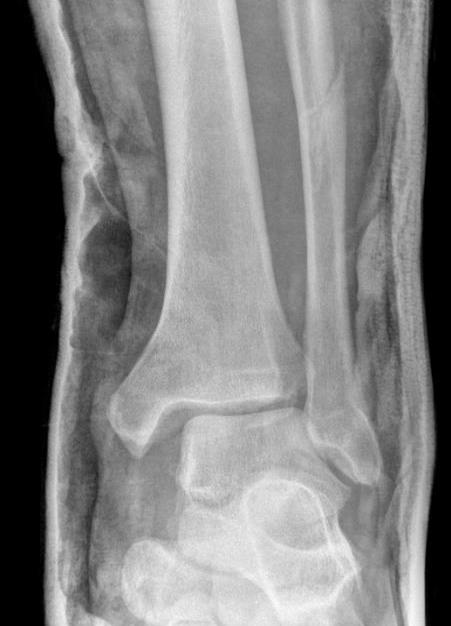

Tibia / fibular overlap < 1mm / syndesmotic injury

Ankle Fracture Syndesmosis WidenedAnkle Diastasis